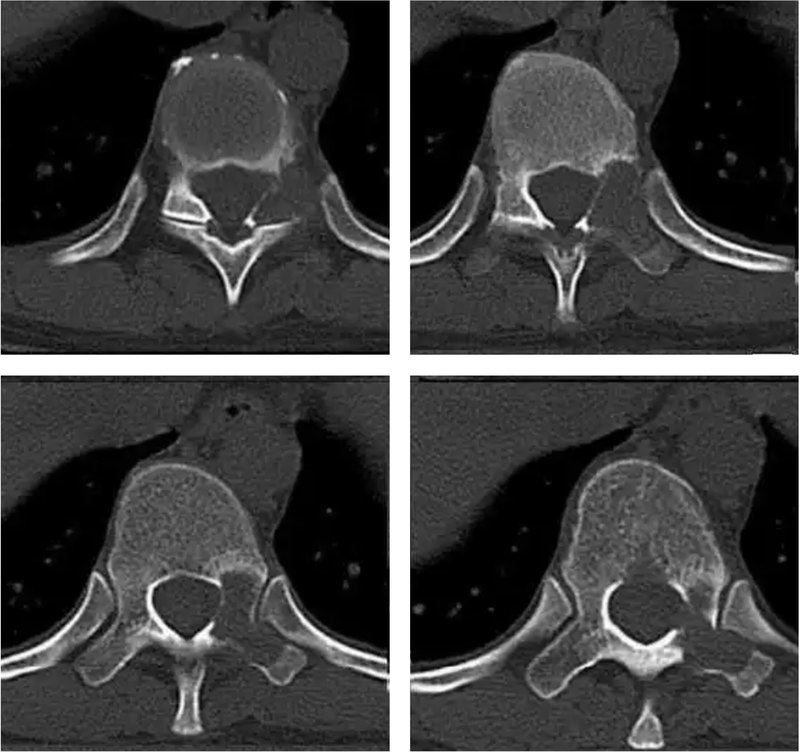

脊椎成骨細胞瘤(骨母細胞瘤)

成骨細胞瘤也稱骨母細胞瘤,占原發(fā)性骨腫瘤的1%,是少見的良性腫瘤,脊椎發(fā)病占全部的30%~40%,其中有55%侵及后方骨結構。椎體受累并不少見,但原發(fā)于椎體者卻很少。從頸椎到腰椎都可發(fā)病,與骨樣骨瘤相比,發(fā)病年齡稍高,青年時期發(fā)病的多見,90%在20~30歲期間被確診,男性稍多見。過去認為均為良性,并冠以“良性”二字。但通過最近若干年的研究,發(fā)現(xiàn)有的以后出現(xiàn)局部浸潤和復發(fā),最后發(fā)生遠處轉移而導致患者死亡,文獻中陸續(xù)出現(xiàn)冠有“侵襲性”或“惡性”的名稱,現(xiàn)已將成骨細胞瘤分成良性和惡性。良性成骨細胞瘤病理形態(tài)與骨樣骨瘤相似,目前兩者尚無特殊的組織學標準來區(qū)別,但從癥狀和影像上可以鑒別。與出現(xiàn)夜間劇痛的骨樣骨瘤不同,成骨細胞瘤多伴有局部的鈍痛,這種鈍痛多提示其為神經癥狀性側彎的原因。成骨細胞瘤好侵犯髓質,病灶較大,直徑多在1.5~2.0cm以上,而且10%~15%呈動脈瘤樣骨囊腫樣改變,周圍無廣泛骨質硬化。脊椎成骨細胞瘤以腰椎最多,胸椎次之??砂l(fā)生在松質骨與皮質骨,椎弓根最容易受累,只有當腫瘤相當大時才累及椎體。所有脊椎成骨細胞瘤患者均有疼痛,脊柱活動受限,活動時可引起放射痛,休息后緩解,可有脊柱側凸,病變位于主彎頂點的凹側,隨著病變發(fā)展可出現(xiàn)神經根受壓刺激癥狀,如麻木、肌肉無力、反射改變、直腿抬高試驗陽性等。嚴重者有脊髓壓迫癥狀,也可發(fā)生病理性骨折。X線片主要表現(xiàn)為膨脹性溶骨性破壞,在破壞區(qū)內有反應性新骨形成與不同程度的鈣化斑,界限清楚,無廣泛性骨質硬化,常見皮質穿破及軟組織腫塊,有的可以很大,邊緣常有一層鈣化殼,軟組織腫塊中也可看到一些細小的不規(guī)則的鈣化點。根據X線片表現(xiàn)分為三種類型:①與骨樣骨瘤相似,中心部為骨透亮影(其內部有鈣化),周圍為骨硬化緣;②內部有許多小的鈣化,邊緣呈鈣化的隆起型骨改變,此類型最常見;③骨浸潤破壞嚴重,即炎癥波及骨壞死或軟組織內部。CT可幫助了解病變范圍及與周圍組織的毗鄰關系。MRI所見是非特異性的,T1加權像呈低信號,T2加權像呈高信號。從影像上來看,與骨樣骨瘤鑒別的要點是該腫瘤大小超過1.5~2.0cm,而且有骨的隆起型改變,伴有軟組織病變,與中心性鈣化的骨樣骨瘤不同的是,成骨細胞瘤呈多中心的軟骨組織鈣化。良性成骨細胞瘤,盡可能徹底切除腫瘤椎弓或椎體,多數可治愈,復發(fā)率為10%~15%。惡性成骨細胞瘤,盡可能邊緣性切除腫瘤椎弓或椎體,復發(fā)率為50%。不論良、惡性成骨細胞瘤,若有脊髓受壓表現(xiàn)者,均應作腫瘤切除、脊髓減壓術。腫瘤切除后缺損區(qū)小而不影響脊柱穩(wěn)定性者,可植骨或填充骨水泥;切除后缺損區(qū)大,脊柱穩(wěn)定性遭到破壞者,需用內固定器械加植骨或骨水泥來重建脊柱的穩(wěn)定性。對某些手術有困難的部位或不具備手術條件者,可給予放射治療。惡性成骨細胞瘤術后可行輔助放療或多種藥物聯(lián)合化療。注意定期隨訪,發(fā)現(xiàn)復發(fā)時可再次手術。